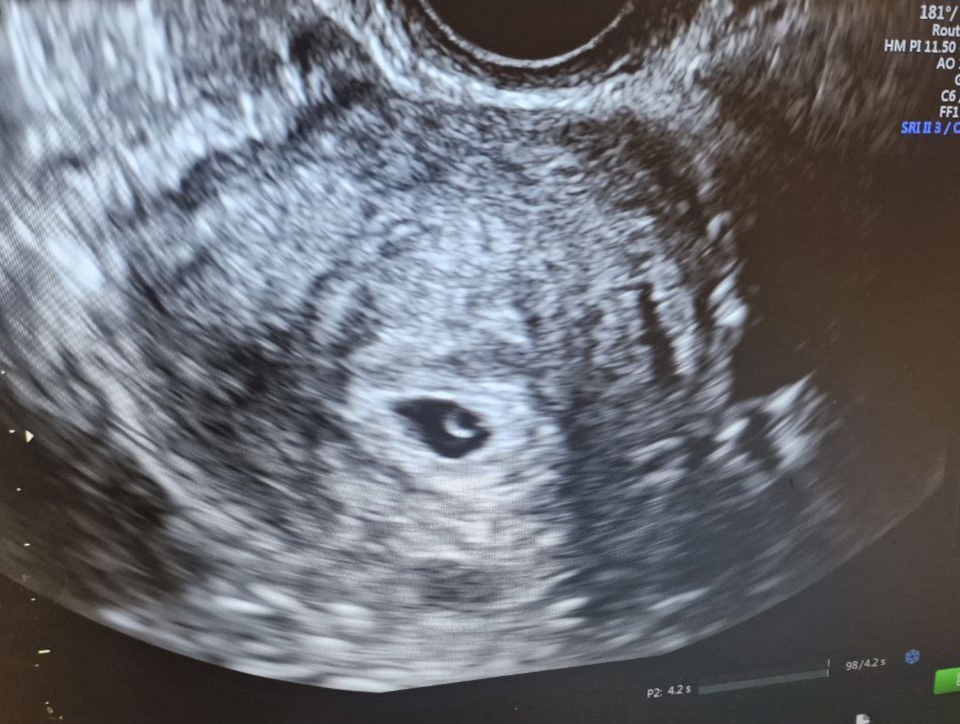

• комплексній діагностиці разом з УЗД або гістероскопією;

УЗД органів малого тазаНеінвазивнийНе потребуєНизька для клітинних змінНемаєСкринінг, оцінка товщини та структури ендометрію